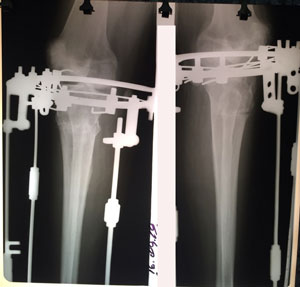

рентген в 60 дней

IMG_5871-16-09-19-08-44.JPG

IMG_5870-16-09-19-08-44.JPG